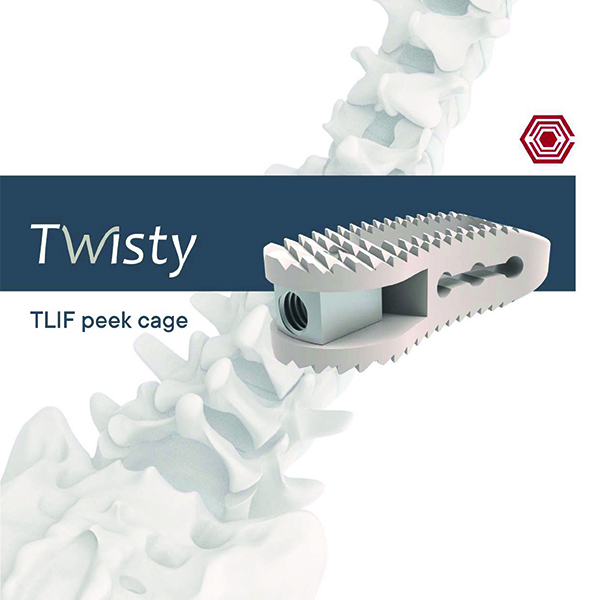

Twisty Tlif Peek Cage

Akif Kaya Aybek

Norm Akademi

- Surgical Technique

- Size of Implants

- Instrument Container

- Instrument Types